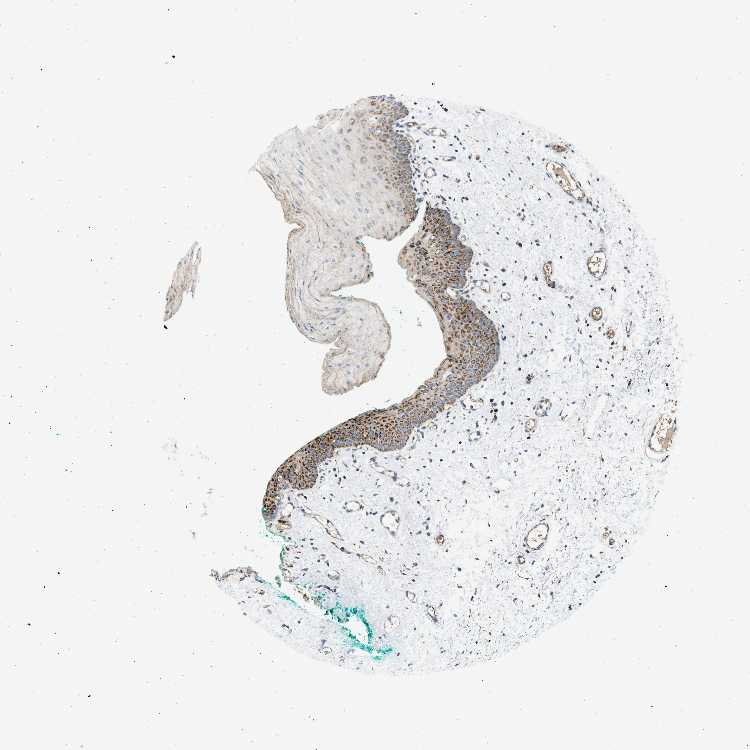

TISSUE PRIMARY DATA ORAL MUCOSA Show tissue menu

ORAL MUCOSA - Antibody stainingi

Antibody staining in the annotated cell types in the current human tissue is reported as not detected, low, medium, or high, based on conventional immunohistochemistry profiling in selected tissues. This score is based on the combination of the staining intensity and fraction of stained cells.

Each image is clickable and will lead to virtual microscopy that enables deeper exploration of all samples and also displays staining intensity scores, fraction scores and subcellular localization as well as patient and tissue information for each sample.

Antibody HPA015665Antibody HPA019185

Squamous epithelial cells HighNot detected